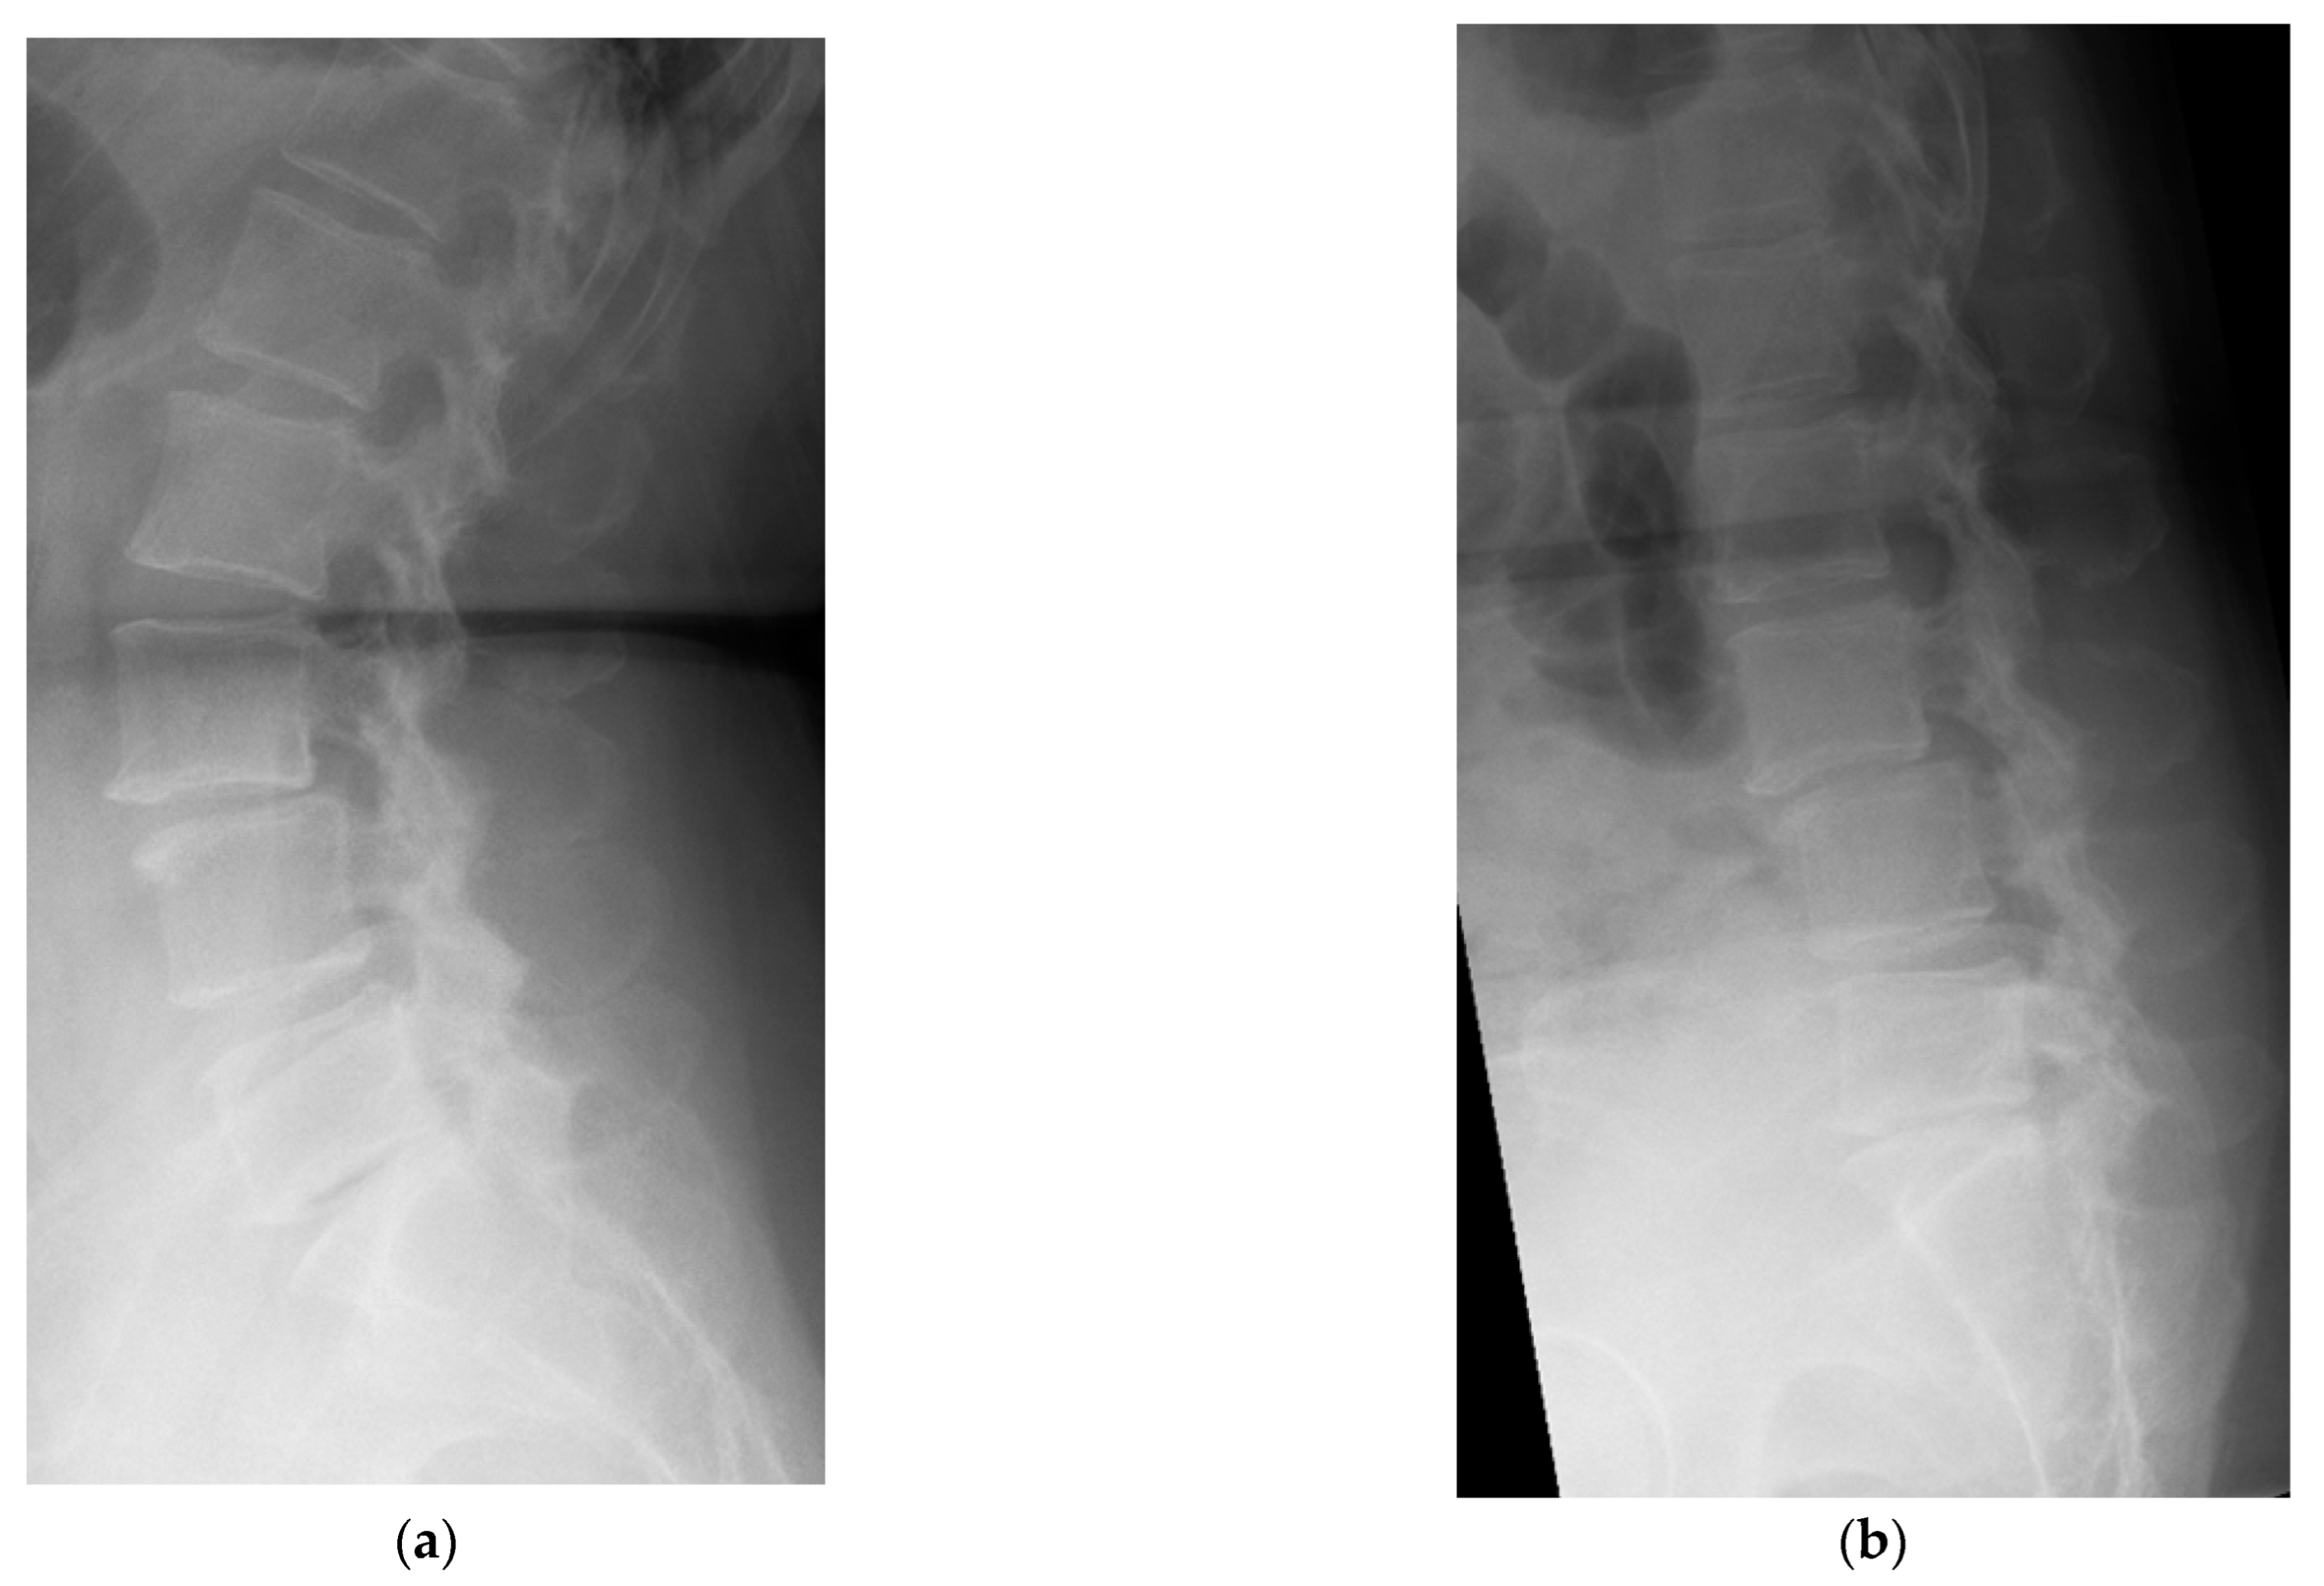

4.1. Case 1: Madam M

4.2. Case 2: Madam R

4.3. Case 3: Madam M